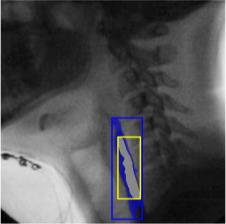

The videofluoroscopic swallowing study (VFSS) is a gold-standard imaging technique for assessing swallowing, but analysis and rating of VFSS recordings is time consuming and requires specialized training and expertise. Researchers have recently demonstrated that it is possible to automatically detect the pharyngeal phase of swallowing and to localize the bolus in VFSS recordings via computer vision, fostering the development of novel techniques for automatic VFSS analysis. However, training of algorithms to perform these tasks requires large amounts of annotated data that are seldom available. We demonstrate that the challenges of pharyngeal phase detection and bolus localization can be solved together using a single approach. We propose a deep-learning framework that jointly tackles pharyngeal phase detection and bolus localization in a weakly-supervised manner, requiring only the initial and final frames of the pharyngeal phase as ground truth annotations for the training. Our approach stems from the observation that bolus presence in the pharynx is the most prominent visual feature upon which to infer whether individual VFSS frames belong to the pharyngeal phase. We conducted extensive experiments with multiple convolutional neural networks (CNNs) on a dataset of 1245 bolus-level clips from 59 healthy subjects. We demonstrated that the pharyngeal phase can be detected with an F1-score higher than 0.9. Moreover, by processing the class activation maps of the CNNs, we were able to localize the bolus with promising results, obtaining correlations with ground truth trajectories higher than 0.9, without any manual annotations of bolus location used for training purposes. Once validated on a larger sample of participants with swallowing disorders, our framework will pave the way for the development of intelligent tools for VFSS analysis to support clinicians in swallowing assessment.